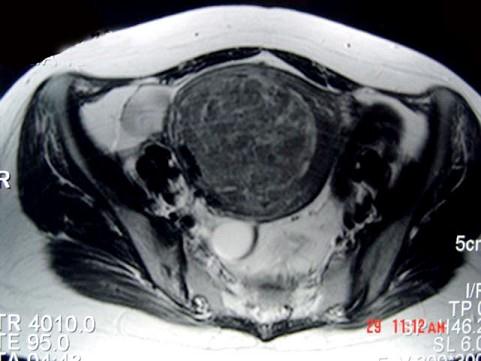

问题 女性,36岁,腹痛,自觉摸到包块,行B超检查提示盆腔内巨大包块,进一步行MRI检查,如图所示,考虑为 ( )

选项 A、卵巢囊肿 B、膀胱憩室 C、子宫腺肌瘤 D、子宫癌 E、子宫肌瘤

答案 C